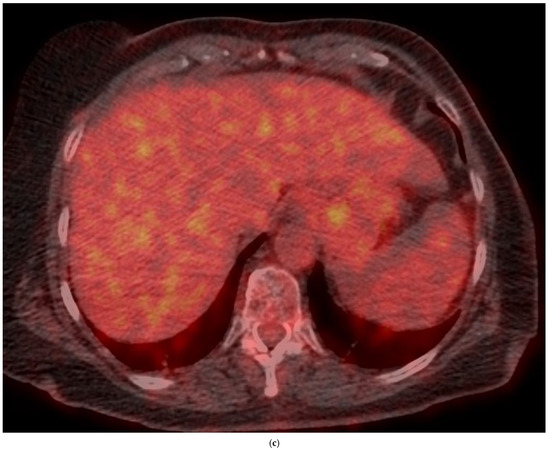

4. Clinical Characteristics of VIAs-Patients